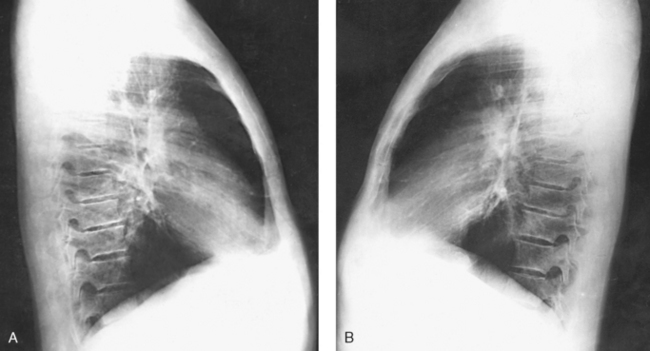

Structures shown: The preliminary left lateral chest position is used to show the heart, the aorta, and left-sided pulmonary lesions (Figs. 10-37 and 10-38). The right lateral chest position is used to show right-sided pulmonary lesions (Fig. 10-39). These lateral projections are employed extensively to show the interlobar fissures, to differentiate the lobes, and to localize pulmonary lesions.

Fig. 10-38 A, Left lateral chest. B, Right lateral chest on same patient as in A. Note the size of the heart shadows.